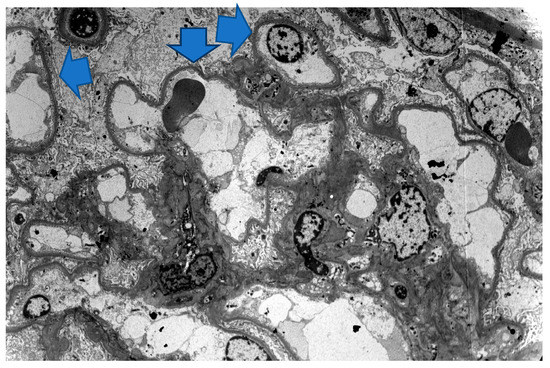

2. Case 1 Description: MCD Associated with Tamoxifen

3. Case 2 Description: MCD Associated with D-Penicillamine

4. Case 3 Description: D-Penicillamine-Associated MCD

5. Case 4 Description: Pembrolizumab-Axitinib-Induced MCD